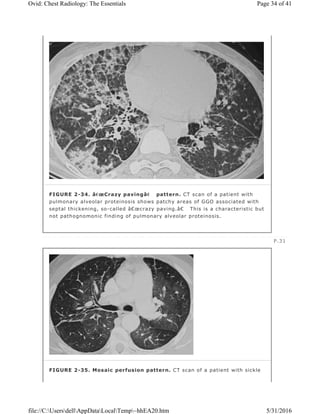

Diffuse or patchy GGO is frequently the main abnormality seen in the acute or

subacute phase of extrinsic allergic alveolitis. It is also the predominant finding

in patients with desquamative interstitial pneumonia, in which it reflects the

presence of mild interstitial thickening and filling of the airspaces with

macrophages. In pulmonary alveolar proteinosis, the areas of GGO usually have

a patchy or geographic distribution. Although the abnormality consists mainly of

filling of airspaces with proteinaceous material, interlobular septal thickening is

frequently identified on CT in the areas of GGO, creating a “crazy pavingâ€

pattern (Fig. 2-34). Solitary small areas of GGO can signify early stage

bronchioloalveolar carcinoma or atypical adenomatous hyperplasia (AAH).

FIGURE 2-34. “Crazy paving†pattern. CT scan of a patient with

pulmonary alveolar proteinosis shows patchy areas of GGO associated with

septal thickening, so-called “crazy paving.†This is a characteristic but

not pathognomonic finding of pulmonary alveolar proteinosis.

FIGURE 2-35. Mosaic perfusion pattern. CT scan of a patient with sickle

Page 34 of 41Ovid: Chest Radiology: The Essentials

Mosaic Pattern of Lung Attenuation

Lung attenuation normally increases during exhalation. In the presence of airway

obstruction and air trapping, lung remains lucent on exhalation and shows little

change in cross-sectional area; this is best appreciated when patchy and

compared to normal lung. Areas of air trapping are seen as relatively low in

attenuation on expiratory CT scans. Areas of air trapping can be patchy and

nonanatomic; can correspond to individual secondary pulmonary lobules,

segments, and lobes; or may involve an entire lung. Air trapping in a lobe or

lung is usually associated with large airway or generalized small airway

abnormalities, whereas lobular or segmental air trapping is associated with

diseases that affect small airways. Bronchiolectasis is a common associated

finding. Pulmonary vessels within the low-attenuation areas of air trapping often

appear small relative to vessels in the more opaque normal lung regions (27).

This finding is also seen with vascular disease, such as chronic thromboembolic

disease, as a result of decreased perfusion to affected areas of lung.

cell disease shows a mosaic pattern of lung attenuation. The abnormal

lucent areas represent decreased perfusion secondary to microvascular

occlusion.